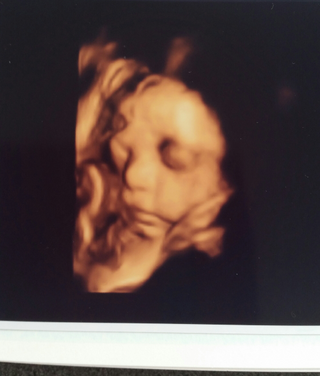

妊娠9ヶ月のエコー写真です 先日やっと顔がはっきりと見え主人とど Yahoo 知恵袋